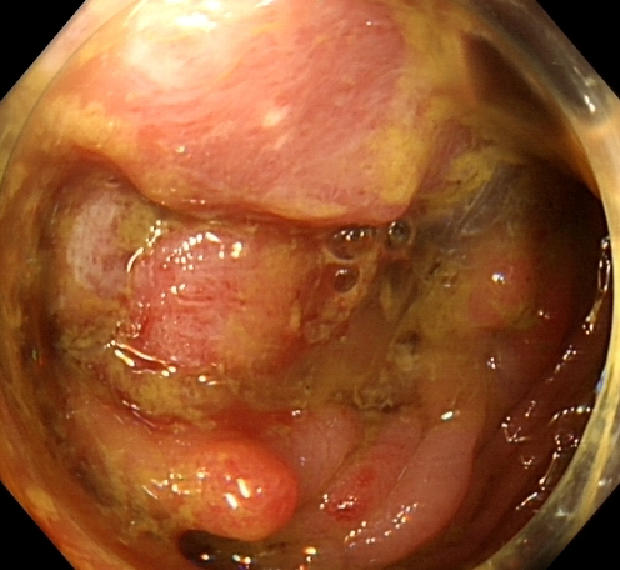

2020-02-04行肠镜检查示:进镜至距肛门30cm见一环腔生长的新生物,表面覆污苔,肠腔狭窄,内镜无法通过,活检质脆,易出血,另直肠见一大小约0.5x0.6cm的扁平息肉,表面光滑,余未见明显异常。

影像结论:结肠癌,直肠息肉。